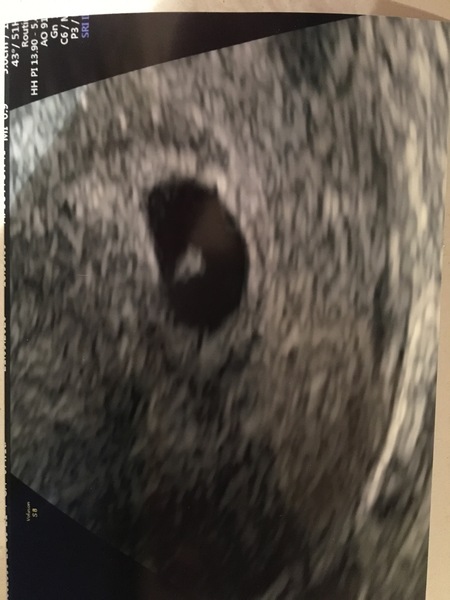

Hi everyone! So we just got back from the private early scan... so relieved to say there was a baby there and a heartbeat!

I thought I was 6+6 but the sonographer said I’m probably more like 5 and a half, which was a surprise. She said that because of my PCOS It’s likely that i ovulated late.

But she said everything is exactly how it should be at this stage so she was really happy. There was a nurse in the room with the sonographer and they were saying it’s one of the earliest they’ve ever been able to pick up on a scan! As usually early scans aren’t recommended til 6 weeks to ensure they can see something.

I’m so happy to have seen a heartbeat and that there was nothing untoward at this stage, obviously I know so much can still go wrong and I guess I’m slightly disappointed to not be further along because I just want to get to 12 weeks.

But it’s our first pregnancy and it was really amazing to see it there!

Does anyone else here have pcos or have ovulated late/got an earlier date at your scan? Xxx